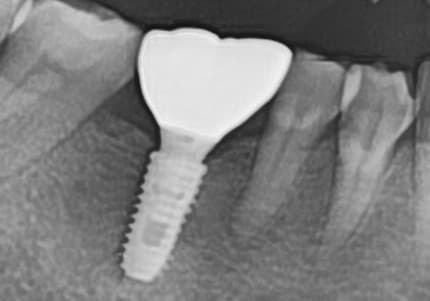

"Suyak juda ko'p yemirilgan edi,

milk davolash orqali suyak tiklanib ketdi"

Og'ir milk kasalligi tufayli suyak ko'p yemirilgan holat

Milk davolash va suyak ko'chirish orqali suyak tiklanib, implant muvaffaqiyatli o'rnatildi